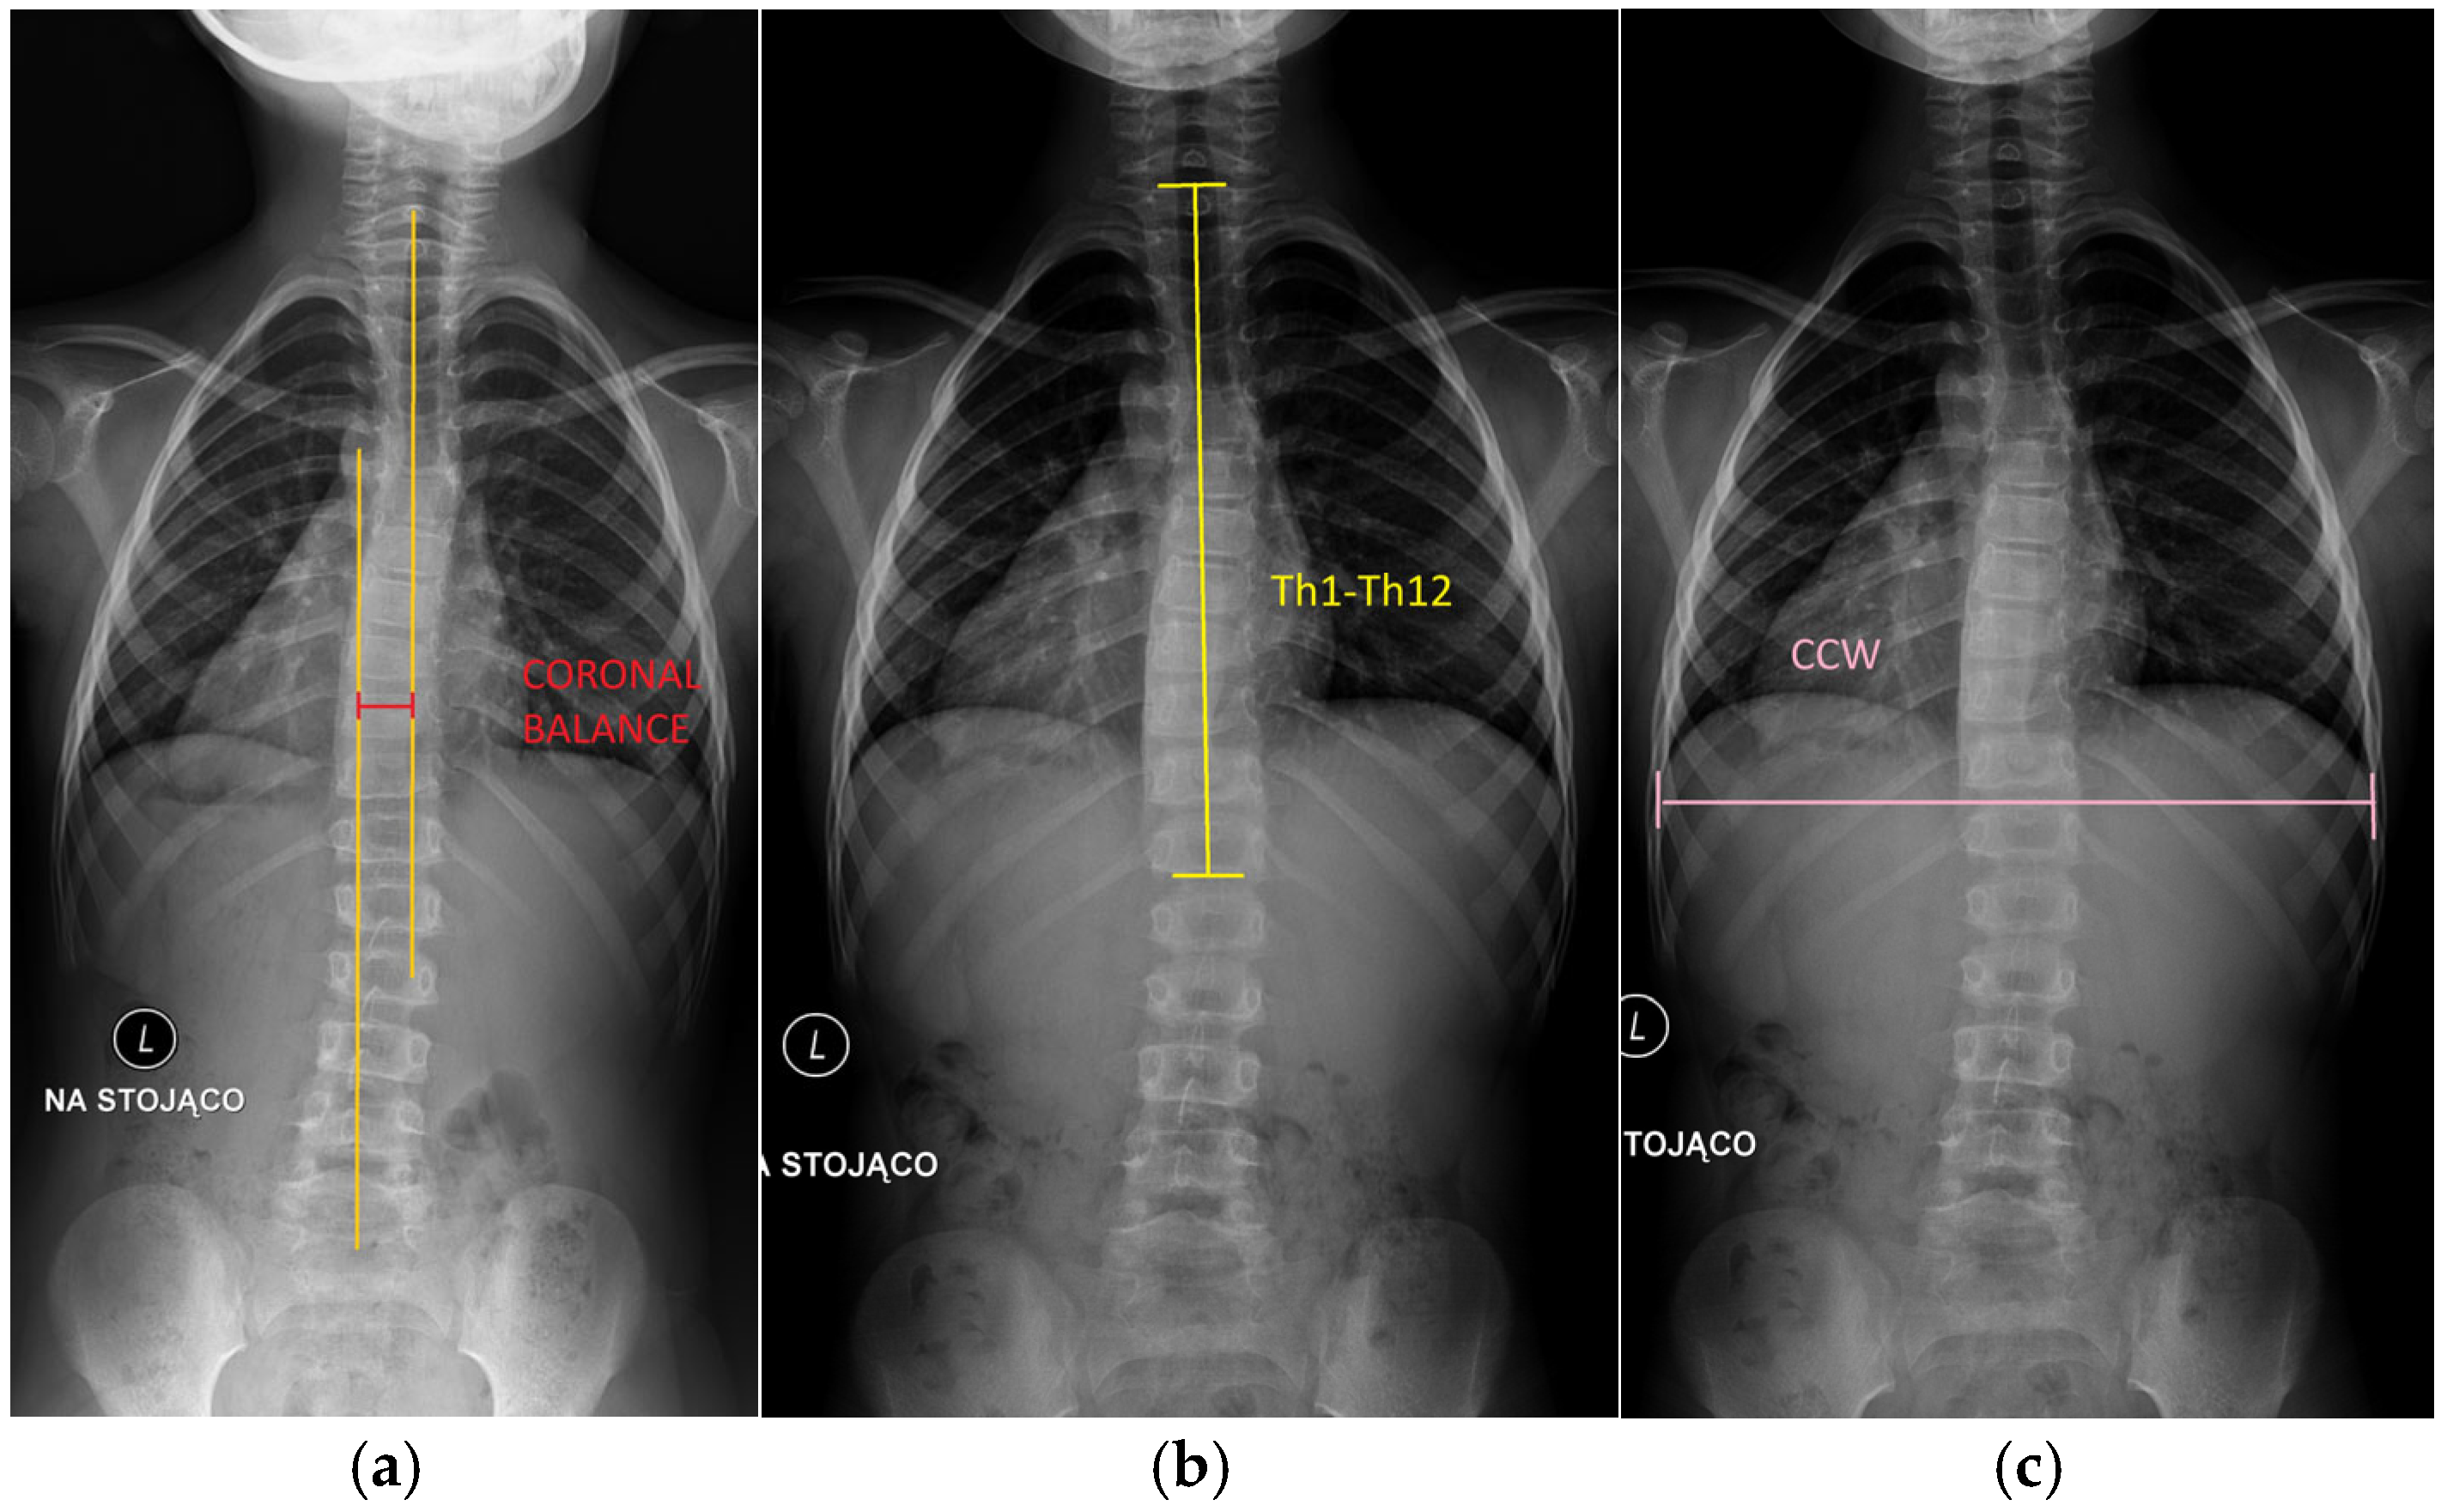

- Coronal balance (cm): Defined as the horizontal distance from the C7 plumb line to the central sacral vertical line (CSVL) on posteroanterior radiographs. A positive value indicates a shift to the right, and a negative value indicates a shift to the left. This parameter reflects overall spinal alignment in the coronal plane (Figure 2).

Figure 2. Measurements used in the manuscript: (a) coronal balance; (b) Th1–Th12 spinal length (the distance between first thoracic vertebra and twelve thoracic vertebra); (c) coronal chest width.

- Th1–Th12 spinal length (cm): Defined as the vertical linear distance from the superior endplate of Th1 to the inferior endplate of Th12 on posteroanterior radiographs, representing thoracic spinal height.

- Coronal chest width (CCW) (cm): Measured on posteroanterior radiographs as the maximal horizontal distance between the medial cortices of the ribs at the level of T8, providing an estimate of transverse thoracic development.

- Space available for lung (SAL) on the left (SAL-L) and right (SAL-R) hemithorax (cm): Determined separately for each hemithorax as the vertical distance from the midpoint of the most cephalad rib to the center of the ipsilateral hemidiaphragm [13] (Figure 3).